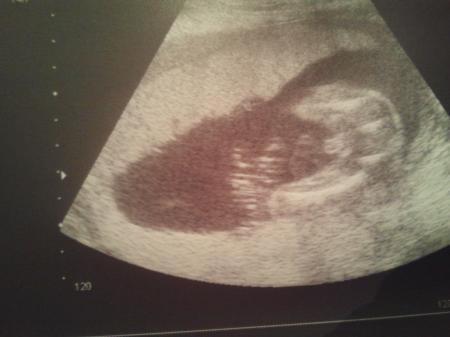

der penis war selbst für mich zu erkennen. 16ssw

hatte auch immer im gefühl es wird ein mädchen,aber man konnte ab der 12 ssw mit immer höher werdener prozentzahl sagen das es ein junge wird.....und habe in der 21 ssw ein beweisbild vom jungen bekommen was sich bis heut nicht geändert hat lg stromi 37 ssw

Bei uns war es auch eindeutig.

Bei uns war es auch sehr eindeutig,habe auch ein foto mit sein bestes stück :)) und im mutterpass wurde es auch eingetragen,denke auch das es bei jungs doch gut erkennbar ist ... ich hatte zwar auch immer das gefühl das es ein mädel sei,aber war/ist nicht!! hauptsache ist es doch das es gesund und munter ist :))

also ich war fester überzeugung das ich ein Mädchen bekommen würde..... In der 16SSW war da nen kleines SChniepelchen und die Ärztin meinte zu 90%nen Junge sollte mich aber noch gedulden... Nun FD in der 20SSW und eindeutig immernoch nen Junge. Das habe selbst ich gesehen hätte sie gar nix sagen müssen. Ärztin meinte auch deutlicher geht es nicht mehr. Und Nabelschnur und Penis konnte man vom aufbau her selbst als Laie deutlich unterscheiden auf dem US Aber irrtümer gibt es immer wieder